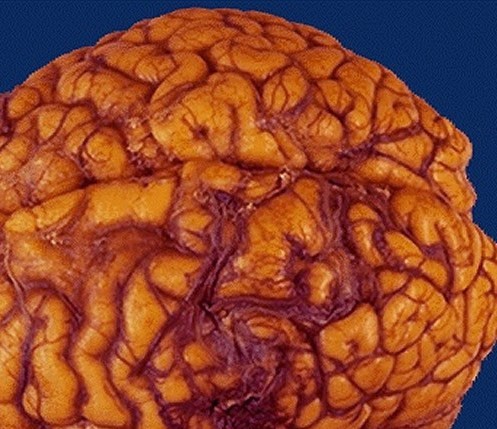

Tanatología-Necropsia